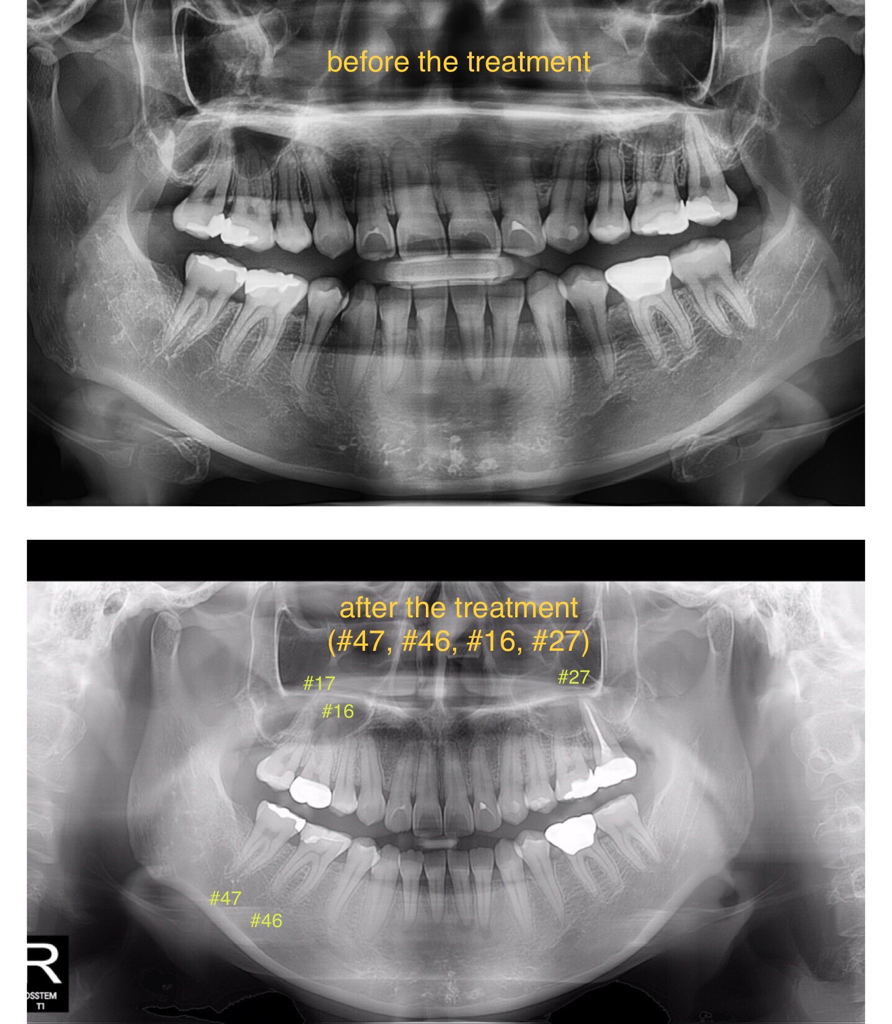

그동안 여러 치과에서 다양한 진단을 들으셔서 혼란스러우셨을텐데 사실 치아 크랙의 경우 정확히 진단이 힘든 경우도 많습니다. 일단 증상이 위 어금니(#17) 인레이 장착 이후 시작되었는지가 중요할 것 같습니다. 보통 인레이 장착 후 느껴지는 불편감은 접착 실패인 경우도 종종 있습니다. 인레이를 했던 치과의 의견이 가장 중요할 것 같습니다.